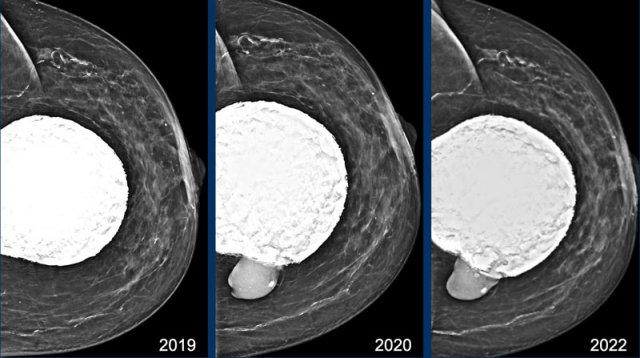

Trên nhũ ảnh năm 2019 cho thấy vôi hóa bao xơ lan rộng và hình dạng rất tròn của túi độn ngực.

Điều này gợi ý co rút bao xơ của túi độn.

Tại lần tái khám năm 2020, đường bờ đã thay đổi và hiện có silicone thoát ra ngoài bao xơ, đây là dấu hiệu xác định của vỡ túi ngoài bao xơ (mũi tên).

Bệnh nhân cao tuổi này không muốn phẫu thuật mà chỉ muốn tầm soát khả năng ác tính.

Tại lần tái khám năm 2022, hình ảnh không thay đổi nhiều. Gel silicone hiện đại có độ kết dính cao hơn và ít có xu hướng lan rộng hơn.